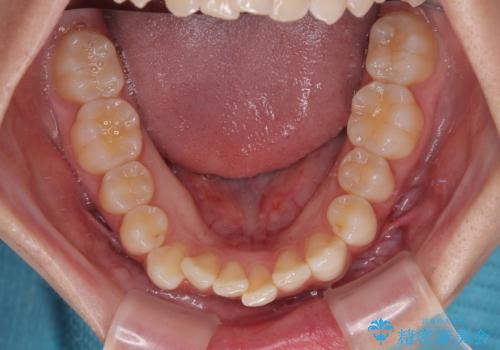

- 上下前歯の重なりを気にして来院された患者様です。

安価なインビザラインパッケージを用いての治療を希望されており、デコボコの程度が中等度であったため、インビザライン・モデレートを用いて矯正治療を行うこととしました。

インビザライン・モデレートは、製作できるアライナーの枚数に制限があるため、移動可能な量に限りがあるものの、インビザライン・ライトよりも枚数が多いため、幅広い症例に対応可能です。